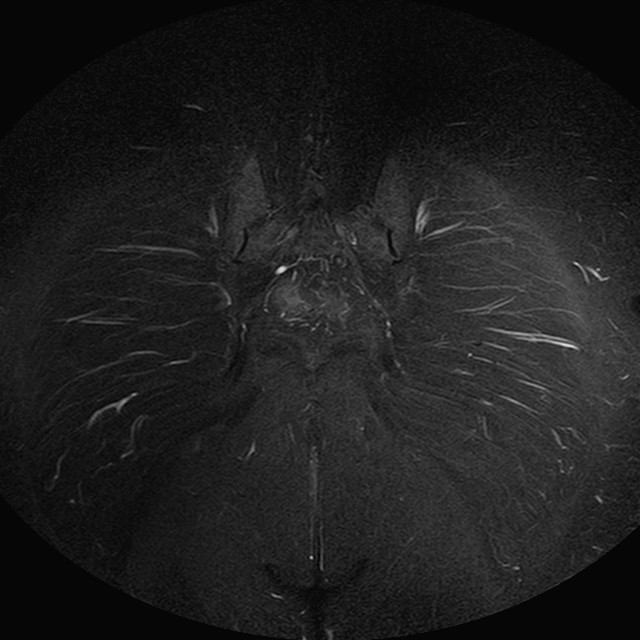

Esami: RMN BACINO

eSTIR

Evidenti e simmetriche alterazioni osteofitosiche in regione coxo femorale con riduzione delle rime articolari. Degenerazione completa del cercine glenoideo. Non attuali segni di versamento articolare. Non segni di edema osseo che escludono attuale algodistrofia od osteonecrosi. Lieve e simmetrica riduzione del trofismo della muscolatura glutea.